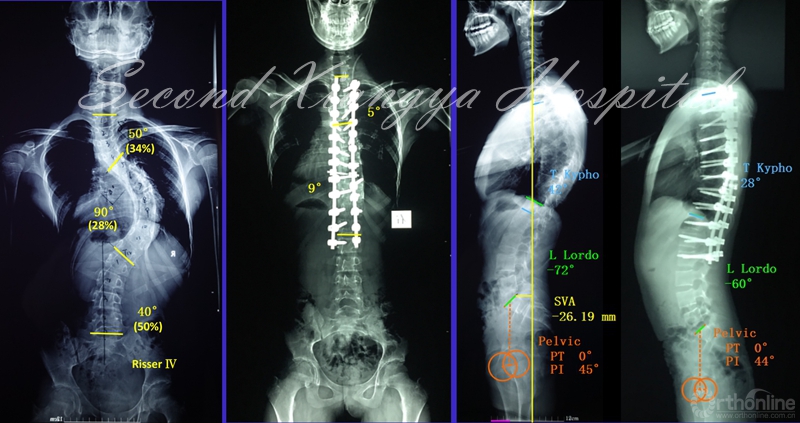

典型病例